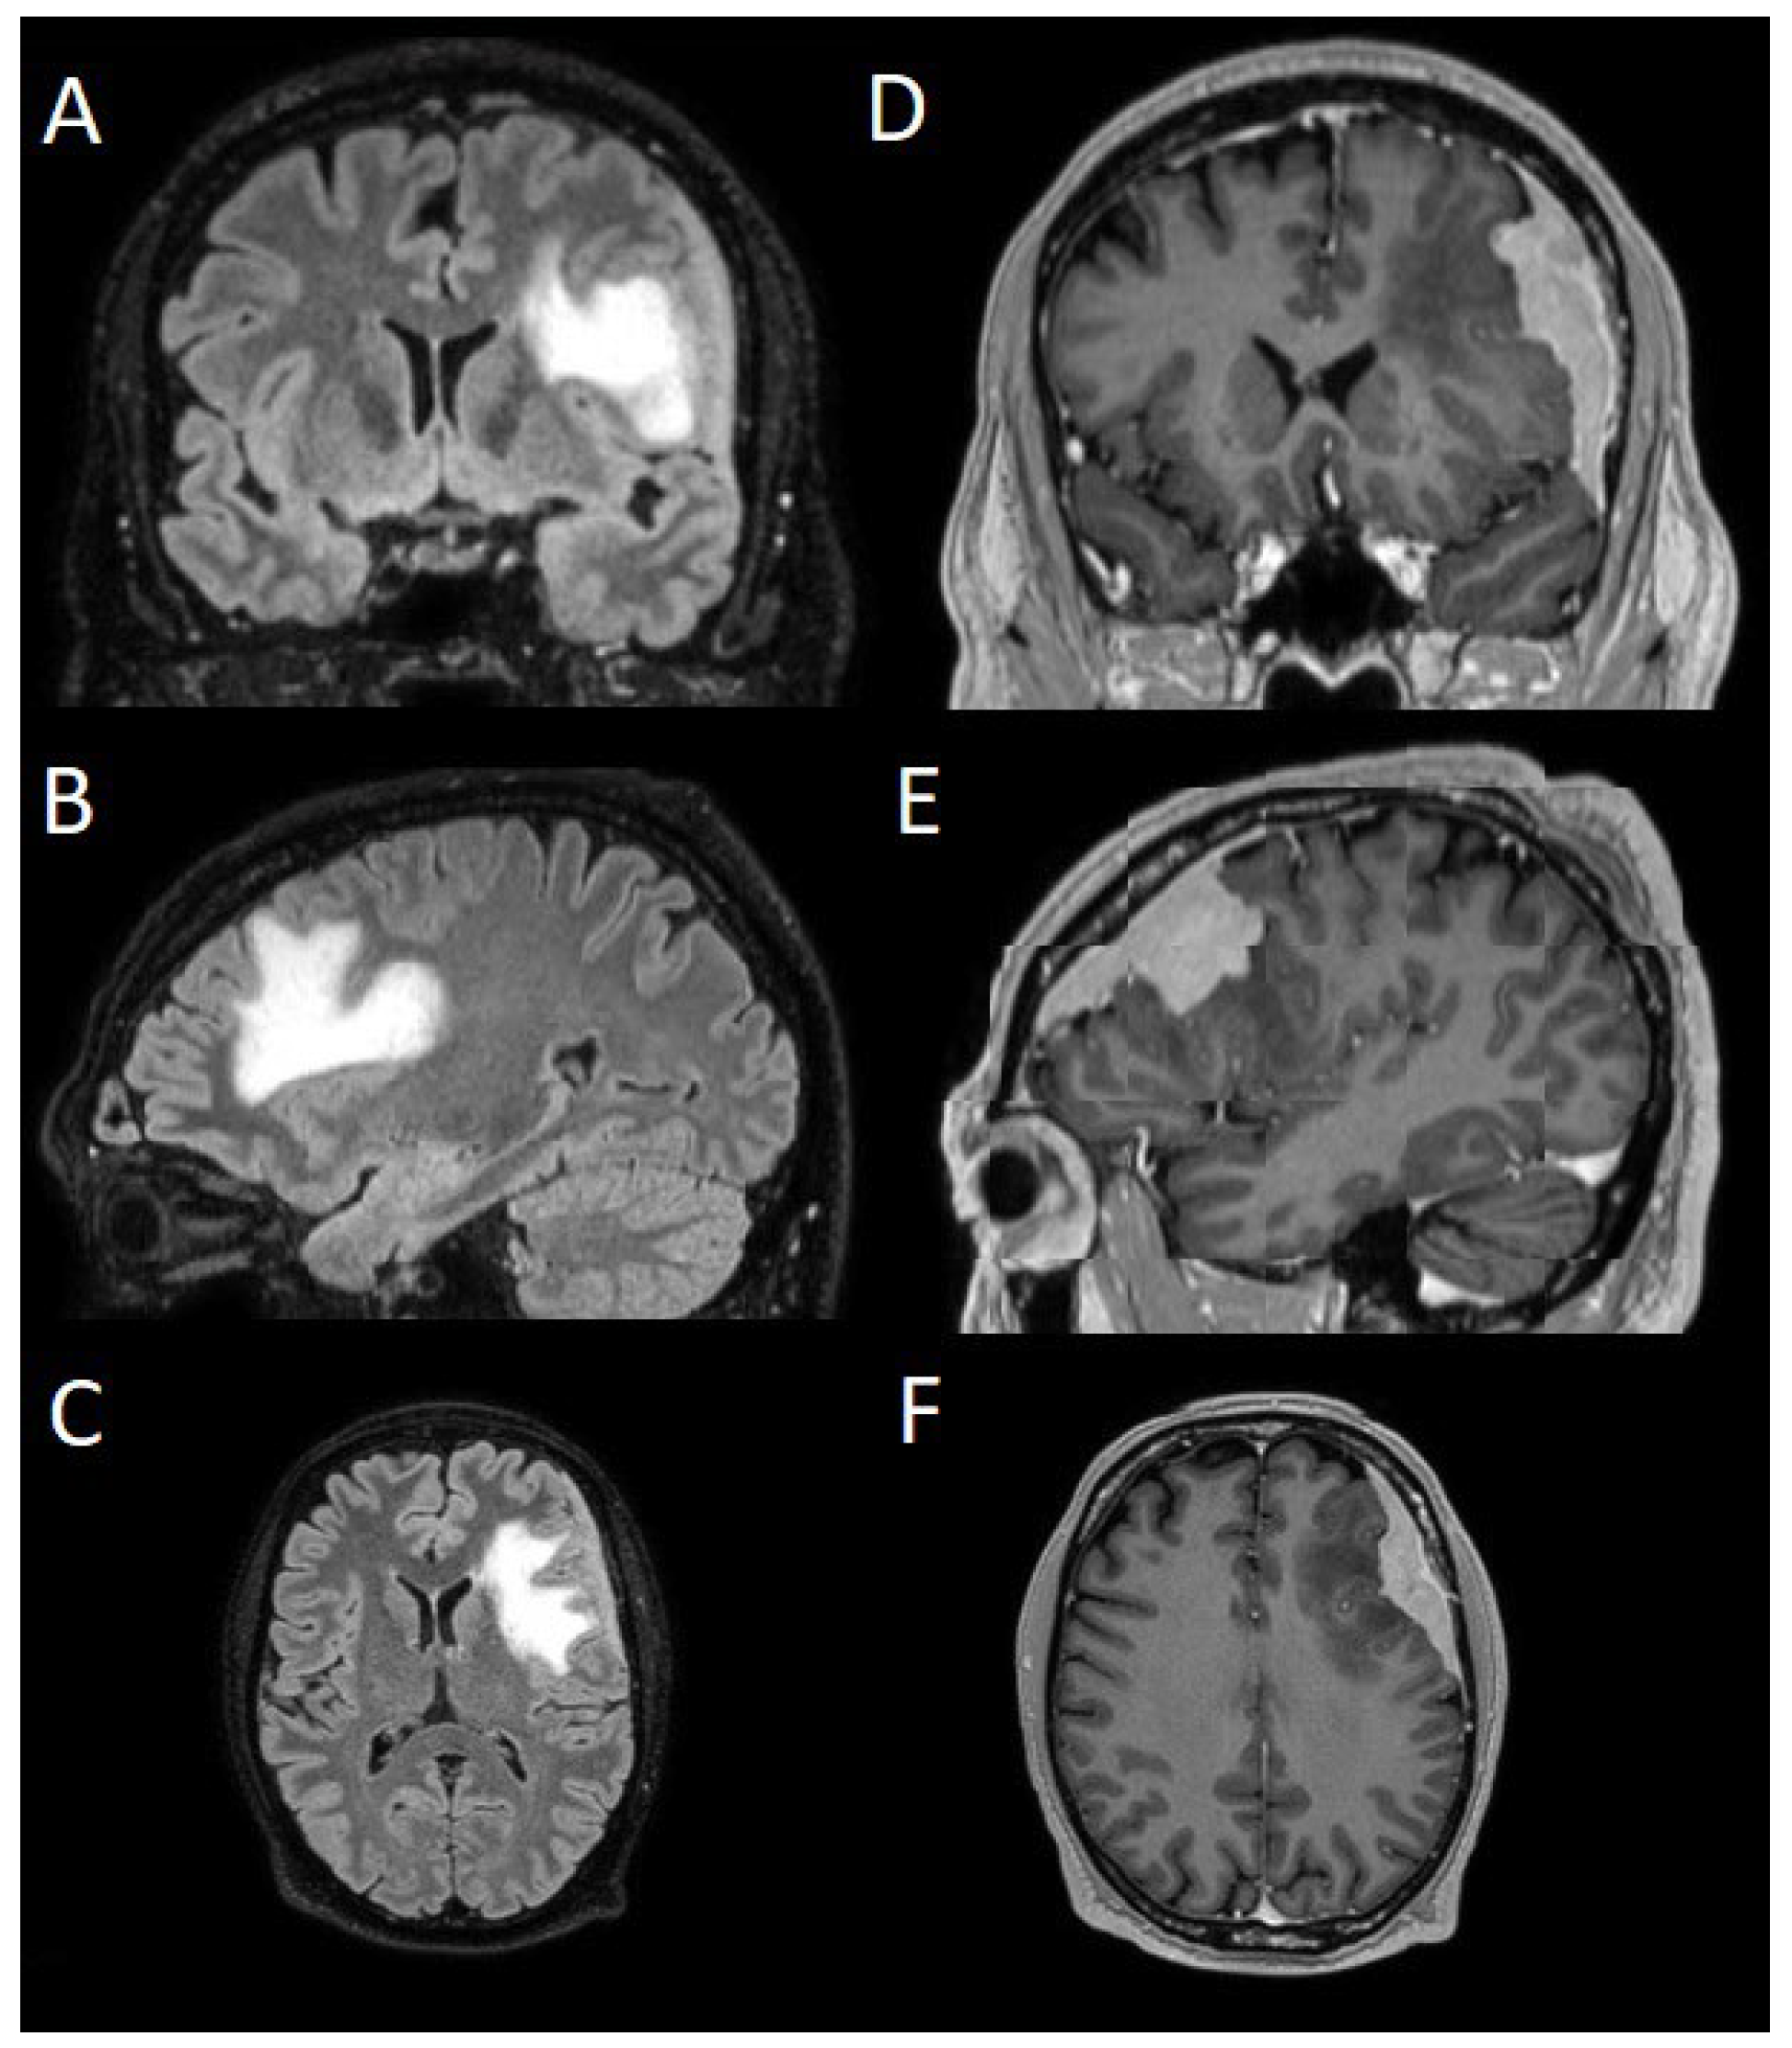

The patients underwent magnetic resonance imaging (MRI) at our Center using a 1.5T or 3T Tesla MRI machine (Ingenia 3T, Philips Medical Systems, Best, The Netherlands) with the standard oncological protocol [7]. Specifically for analysis, the sequences collected were T1-weighted with contrast enhancement to estimate tumor volume and conformation and FLAIR (Fluid-Attenuated Inversion Recovery) to quantify PE (Figure 1). We manage the preoperative imaging in DICOM (Digital Imaging and Communications in Medicine) format. The images from the T1-weighted with contrast enhancement and FLAIR sequences in DICOM format were processed through the Slicer website [12]. Tumor and PE segmentation was performed using a voxel-based analysis that integrated automated and manual methods (Figure 2). The process begins with an automatic thresholding technique to identify initial regions of interest based on intensity values (Figure 2A, 2E). This is followed by manual refinement to enhance accuracy and delineate precise boundaries (Figure 2B, 2C, 2F, 2G). The final segmentation provides volumetric measurements for both the tumor and the PE, aiding in quantitative analysis (Figure 3). The included patients' pre- and post-treatment clinical data were retrospectively extracted from our Center's computerized database. Collected data included demographic information, preoperative clinical details (presence or absence of epilepsy, onset symptoms, ASM therapy and number of ASMs taken, radiological characteristics of the meningioma), and postoperative data (Engel class [10], persistence or discontinuation of ASMs, ASM discontinuation timing, and possible postoperative functional deficits). A single examiner conducted data collection to minimize subjective variability in assessments. Surgical procedures were performed using a transcranial approach under general anesthesia. We excluded cases of surgical resection performed via an endoscopic endonasal approach. Cases of postoperative death (within one year after surgery) were excluded. Cases of WHO grade III meningiomas were excluded. The extent of resection (EOR) was determined based on the postoperative MRI (usually one month after surgery) and classified according to the Simpson grading system [22]. The study included cases of complete macroscopic meningioma resection (Simpson I-II-III). Cases with residual tumor persistence or recurrence after surgery (Simpson IV-V) were excluded (Figure 4). Measurement quantitative data were expressed as mean ± standard deviation (SD). We analyzed qualitative variables by summarizing them as frequencies and percentages, and relationships between variables were assessed using Fisher's exact test and the Chi-square test. Analysis of variance (ANOVA) or "N-1" Chi-squared test was used to assess statistical differences between the two groups or percentages. A p-value < 0.05 was considered statistically significant. ORs and RRs were calculated to assess the statistical significance of associations. ORs were used to measure the strength of association between categorical variables, while RRs were calculated to estimate the risk of an event in one group compared to another. These methods were chosen to assess the significance of relationships between the analyzed variables accurately.

Figure 1. Sequences selected for the segmentation: (A, B, C) coronal, sagittal, axial FLAIR sequences to quantify PE; (D, E, F) coronal, sagittal, axial T1-weighted with contrast enhancement to estimate meningioma volume. FLAIR: Fluid-Attenuated Inversion Recovery; PE: peritumoral edema.